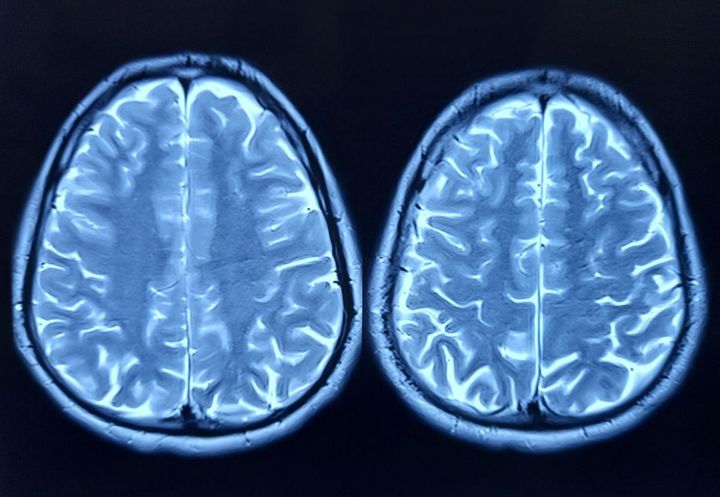

頭部のMRI画像

※写真はイメージです